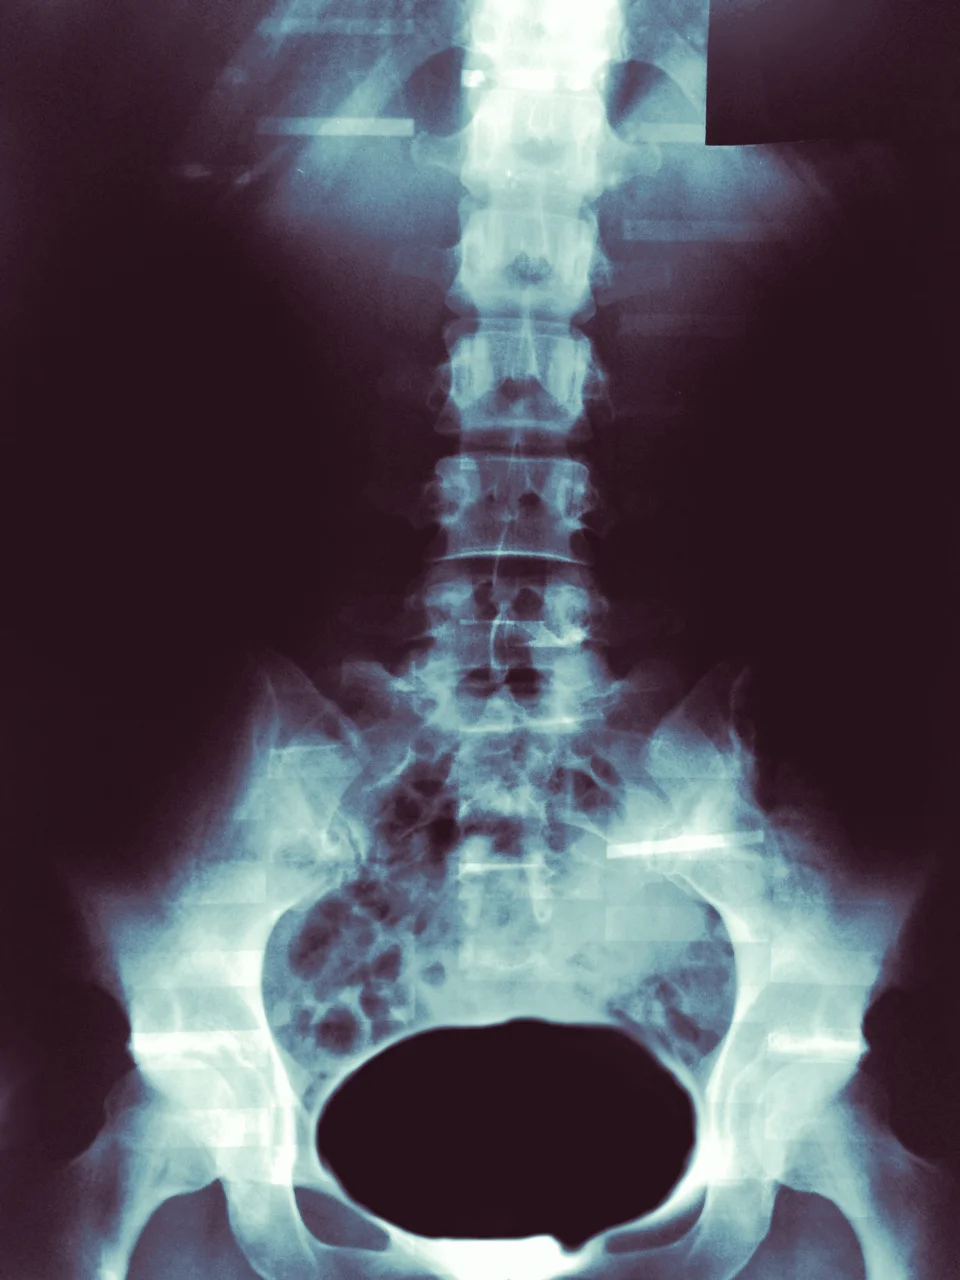

Imaging. It has allowed us to access and see a new world inside of our bodies without cutting beneath the layers. The relative ease of positioning behind an x-ray film or lying down in a tube for an MRI seems very appealing if it allows you to SEE what could be wrong. However, is this really necessary for things such as low back pain or neck pain?

1. These images do not necessarily show you painful structures.

Just because an image shows you that there is a disc herniation or that you have osteoarthritis does not necessarily mean that this is the painful structure. There have been several studies that have shown that when x-rays are performed on non-symptomatic individuals, a large portion of the individuals are found to have typical degenerative processes (such as a “slipped disc” or arthritis), yet they have no pain (1-6, 10-11). This means that for those who are experiencing pain, their image results may be from normal processes and not the true cause of their symptoms. On the other hand, there are other individuals who have significant pain and yet their imaging makes them look as though they are in perfect health.

Most often, when a medical professional has screened a client, ruled out other potential causes for symptoms, and suspects a musculoskeletal problem, the next step is conservative treatment. This includes, but is not limited to, physical therapy, massage, acupuncture, and chiropractics. For instance, a study was performed where 2,500 subjects with acute low back pain were imaged. Remarkably, the researchers found that only one x-ray out of the entire group actually changed an individual’s medical treatment. This is less than 1%, yet more than 40% come into the clinic with imaging already performed. (7) Furthermore, recent findings by a collaboration of physician organizations have determined that x-rays should not be performed on patients with low back pain until the pain lasts longer than 6 weeks for this very reason (9).

Are images useful? Of course. They can augment a PT’s exam findings, but they hold little merit when used alone. On the whole, imaging is not necessary for a musculoskeletal injury unless there has been enough trauma to suspect fracture or disc rupture; there are signs that your symptoms may be originating from somewhere outside the musculoskeletal realm (what we term and scan for called “red flags”); if your prior conservative treatment has not helped improve you symptoms over a 4-6 week period (this may vary); and if you are preparing for something big - like surgery.